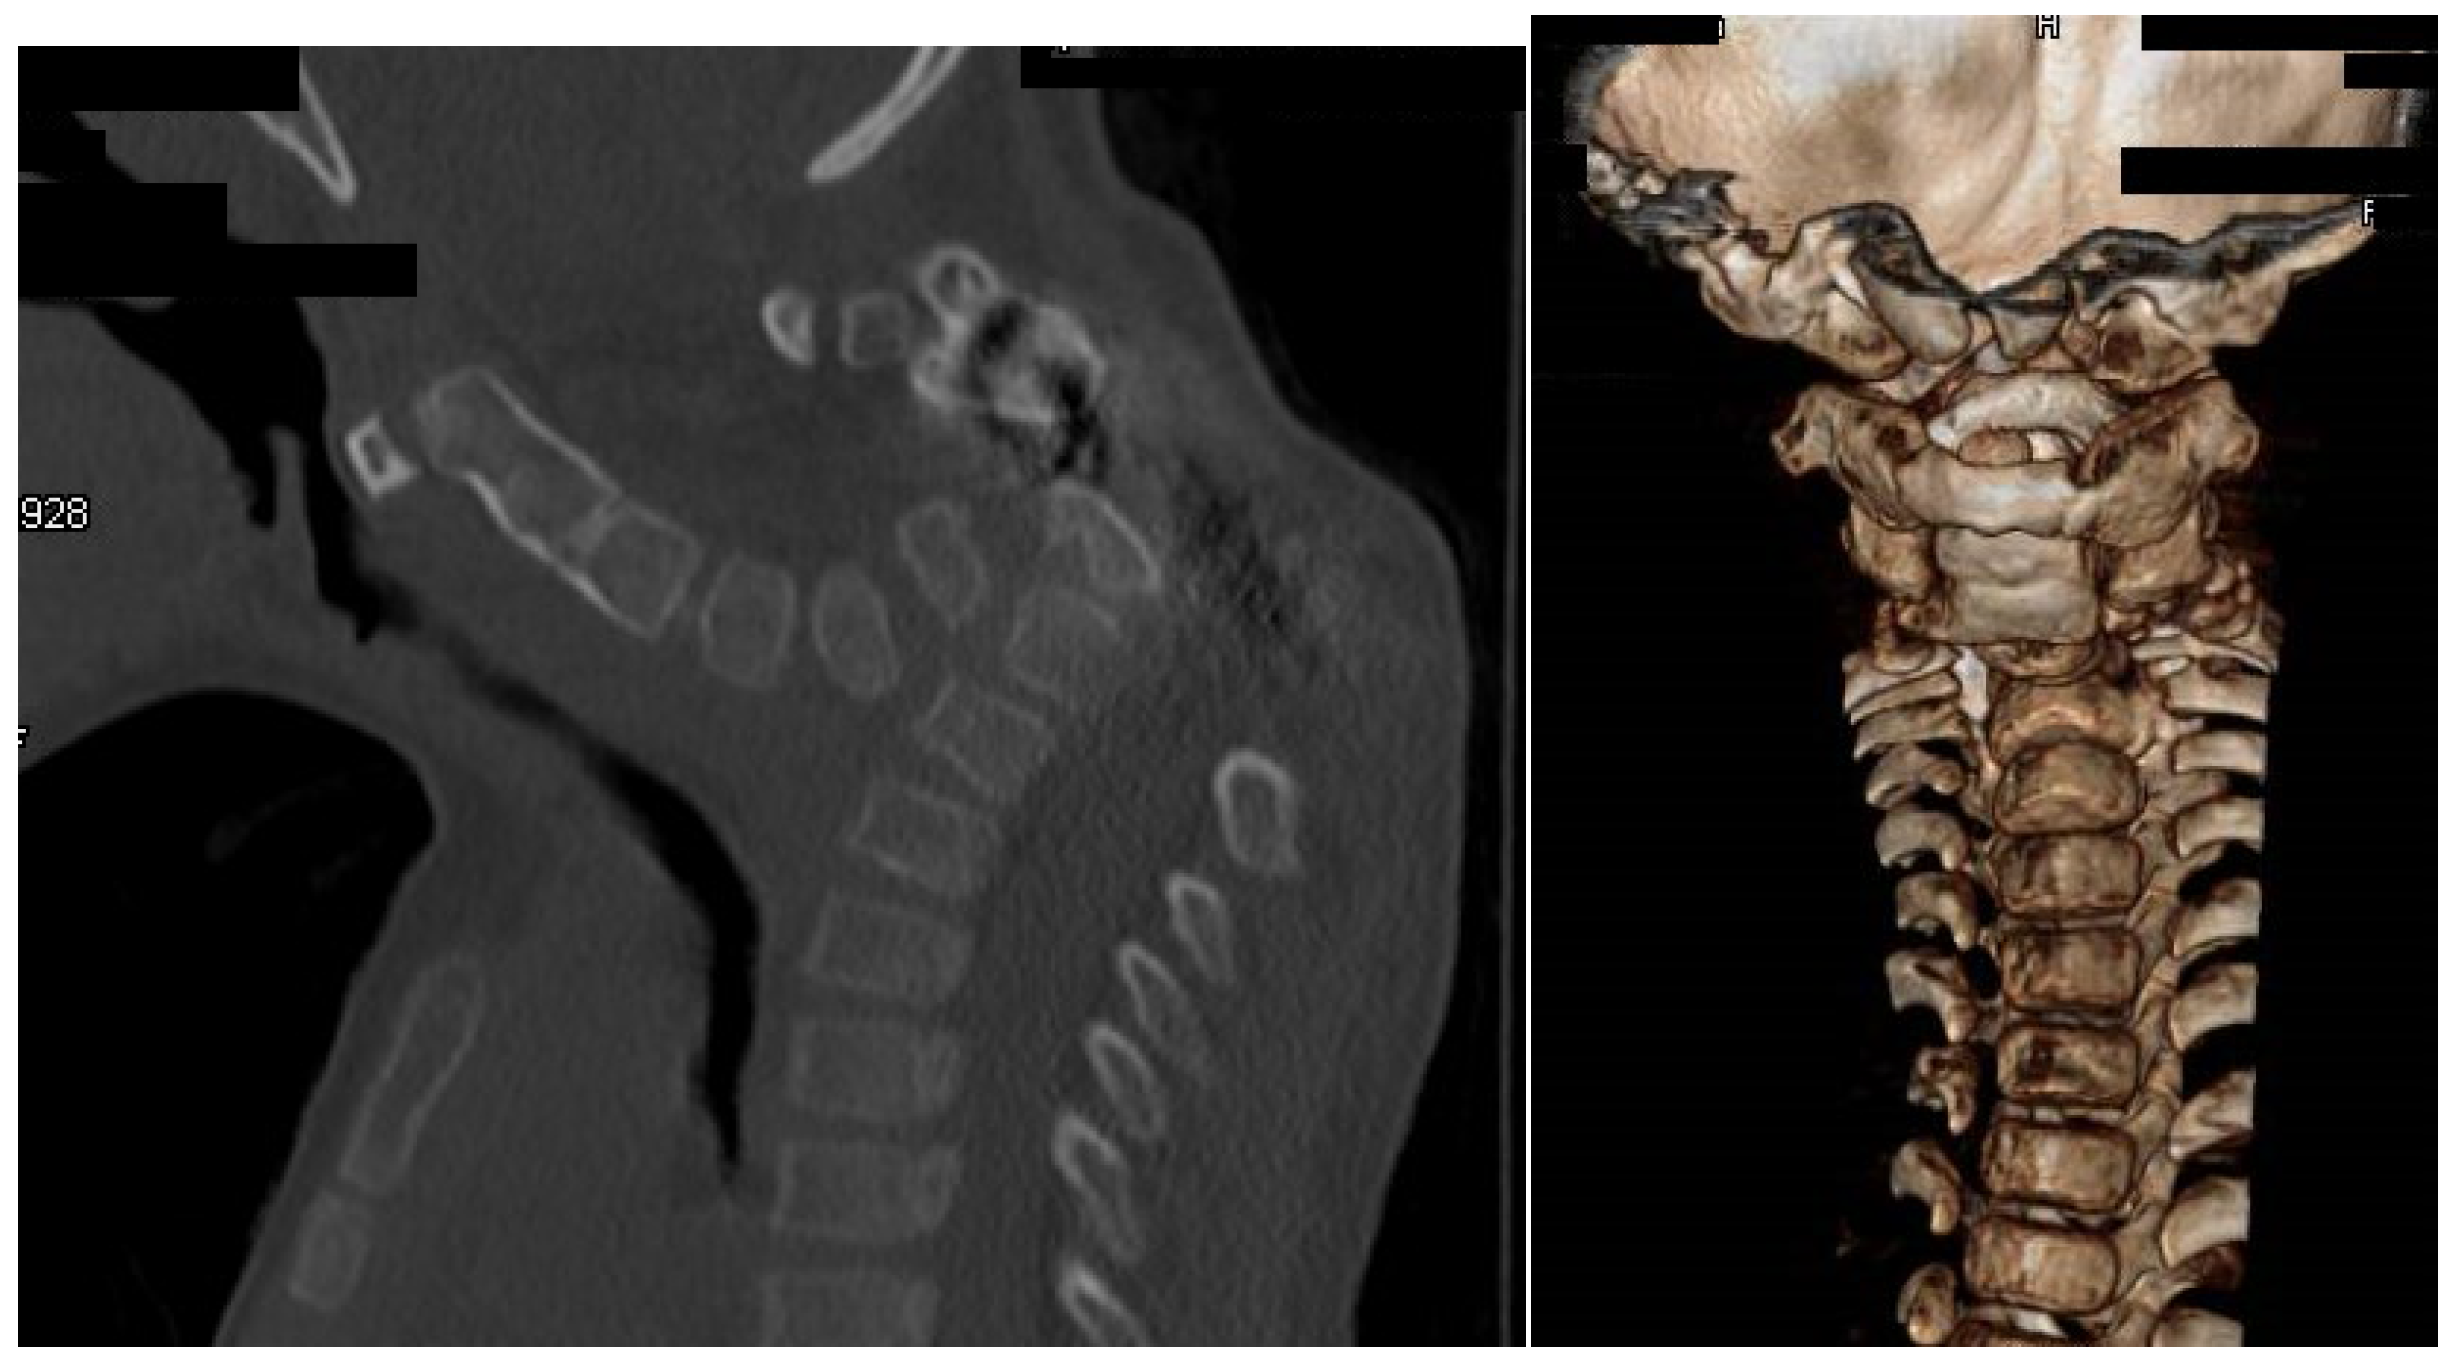

3.3. Acute Angled Kyphosis in A Child with Larsen Syndrome